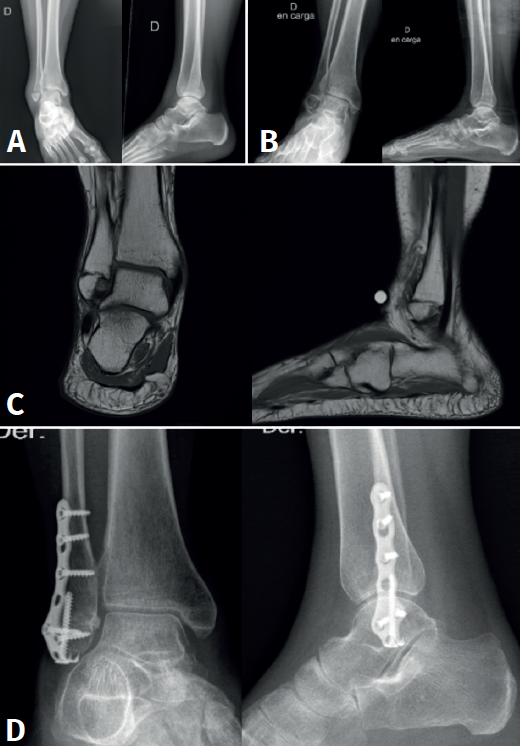

Se trata de una paciente mujer de 44 años sin antecedentes patológicos de interés, con fractura infrasindesmal de peroné y fractura diafisaria del quinto metatarsiano derecho en el contexto de una caída por las escaleras. Ambas fracturas fueron tratadas de manera conservadora con férula de yeso y descarga, y posteriormente con una bota de tipo Walker. Después de un control de 1 año con persistencia del dolor, se evidencia radiológicamente y con una resonancia magnética (RM) presencia de pseudoartrosis a nivel de la fractura infrasindesmal y se decide tratar mediante reducción abierta, fijación interna con placa preconformada distal con gancho y tornillo de compresión a través del foco de la pseudoartrosis, con colocación de injerto óseo extraído de la tibia proximal ipsilateral y chips de esponjosa. En el postoperatorio, la paciente se inmoviliza con una férula de yeso y a la tercera semana con bota de tipo Walker manteniendo la descarga hasta las 6 semanas.

A la séptima semana, la paciente no refiere dolor y se objetiva una consolidación de la fractura a nivel radiológico, por lo que se autoriza el inicio de la deambulación sin limitaciones (Figura 1). Al año postoperatorio, la paciente estaba asintomática y sin dolor.